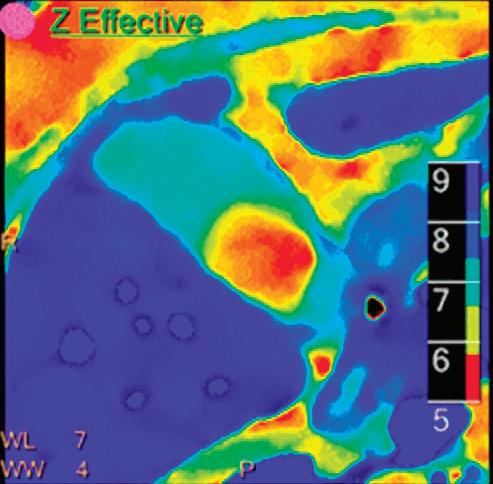

Z Effective (Zeff)

Effective atomic number. Each voxel is set to a value in the range 5 to 30 representing the effective atomic number of that voxel. Z effective of air is set to zero. For reference, Z effective of water is 7.4, Z effective of cortical bone is 13.2, and Z effective of fat is 5.9. Z effective maps are very sensitive to materials characteristics (Figure 3) and can also be used to display perfusion maps and to identify very subtle perfusion deficits (Figure 2b). The accuracy measured on a Gammex phantom with iodine, calcium, and soft tissue inserts show that the majority of Z effective values are within 0.2 Z effective units and are consistent between 120 and 140 kVp scans.21

Patient presented to the emergency department with abdominal pain. The conventional CT does not reveal any abnormality in the gallbladder. In the middle row, spectral attenuation curves reveal two different materials: a first region of interest (purple) with a CT number that is increasing with energy, typical of a low Z effective element (below the Z effective value of water), and a second region of interest (blue) with a CT number that is decreasing with the energy, typical of a Z effective above water. The differentiation between the two materials cannot be performed based on the conventional CT because the two attenuation curves cross each other around 70 keV (where the attenuation is equivalent to the conventional CT). The lower row displays spectral results in the Magic Glass, from left to right: 40 keV image, 200 keV image, iodine density image, and Z effective map. A gallstone is clearly revealed on the 40 keV image and with an inverted contrast on the 200 keV image. The iodine density shows a perfusion defect of the gallbladder wall due to the compression with the gallstone (white arrow), and the Z effective helps us to determine the gallstone composition with a Z effective below 6.5 typical of a cholesterolic composition.